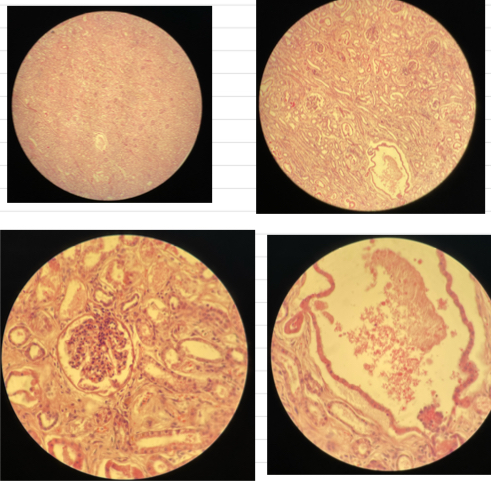

Bacterial embolic purulent nephritis

- bacterial emboli formed in capillary vessels and bv’s

- degen of tubular epi cells

- at edge of bacteria emboli => microabscess (neutrophils w/ debris)

Chronic interstitial nephritis

- inflam (lymphocytes, plasma cells, macrophages) infiltrates in interstitial tissue

- hyperplasia of fibrous tissue

- retention cysts in lower parts of tubules

- atrophy of renal tubules